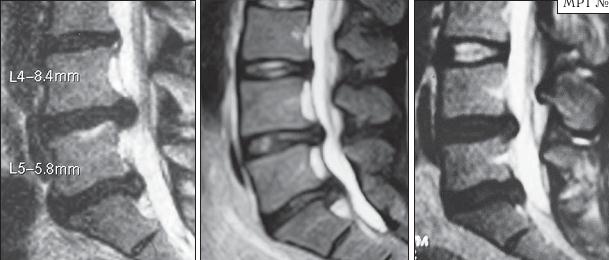

На серии МРТ № 26 наблюдаются секвестрированные грыжи межпозвонковых дисков в поясничном отделе позвоночника в сегментах LIV—LV LV—SI с каудальной (каудальной — расположенной ближе к нижней части туловища, направленной вниз) миграцией секвестра (фрагментов межпозвонкового диска) МРТ № 27 ![]() На серии МРТ № 27 наблюдаются секвестрированные грыжи межпозвонковых дисков в поясничном отделе позвоночника в сегментах L]-Sl с краниальной (вверх) миграцией секвестра (фрагментов межпозвонкового диска) Должен заметить, что по моим наблюдениям, к сожалению, практически все существующие на сегодняшний день методы лечения дегенеративно-дистрофического процесса, в том числе и осложнённого грыжами межпозвонковых дисков, направлены на устранение болевого синдрома. Проще говоря, лечат следствие, а не причину! Обращаю ваше внимание на следующий факт. Бывают грыжи межпозвонковых дисков, которые не вызывают никакой симптоматики, так называемые «немые» грыжи. Как правило, они имеют срединную локализацию. Некоторые «специалисты», практикующие в области вертебрологии, ошибочно считают, что такие грыжи абсолютно безопасны и лечить их нет необходимости. При этом навязывают своё (в данном случае необоснованное, ошибочное) мнение, что межпозвонковые грыжи опасны лишь тогда, когда вызывают боли. К сожалению, это далеко не так! МРТ № 28